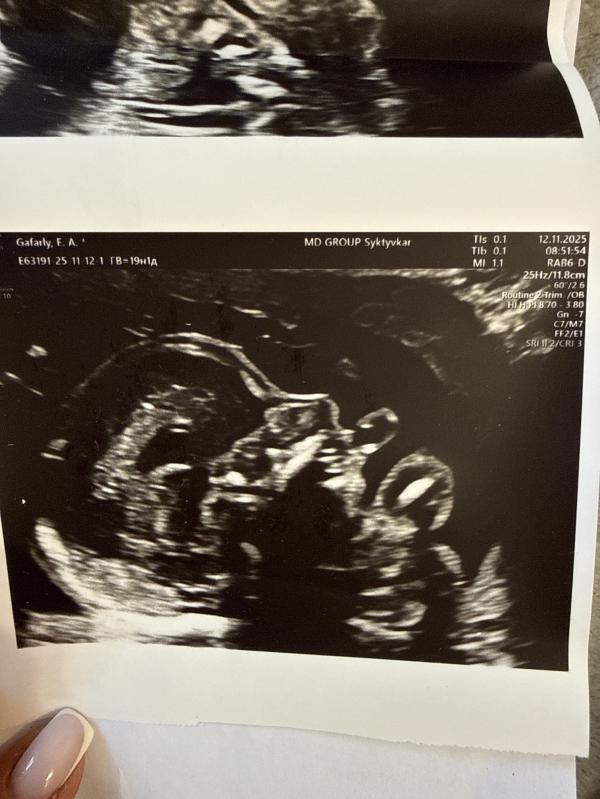

Итак, первое узи, врач Турубанова Р.В. Клиника «Мать и дитя»: беременность 19 недель 1 день. Маркеры ХА: укорочение носовой кости, утолщение шейной складки, гипоплазии и гиперэхогенная структура почек, гиперэхогенный кишечник, ЕАП. Высокий субаортальный ДМЖП. ДМПП первичный (АВК?). Низкая плацентация.

Второе узи, врач Винницкая Т.М. ГБУЗ РК «КРКПЦ»: беременность 19 недель 6 дней. ЗРП. МХА: ЕАП. Гипоплазия назальных костей, расширение полости промежуточного паруса, микрогения. Также на этом узи мы вместе с врачом увидели низко расположенные ушные раковины, это типично для такого синдрома, как и микрогения.

Ниже прикреплю фотографии узи и фото с узи